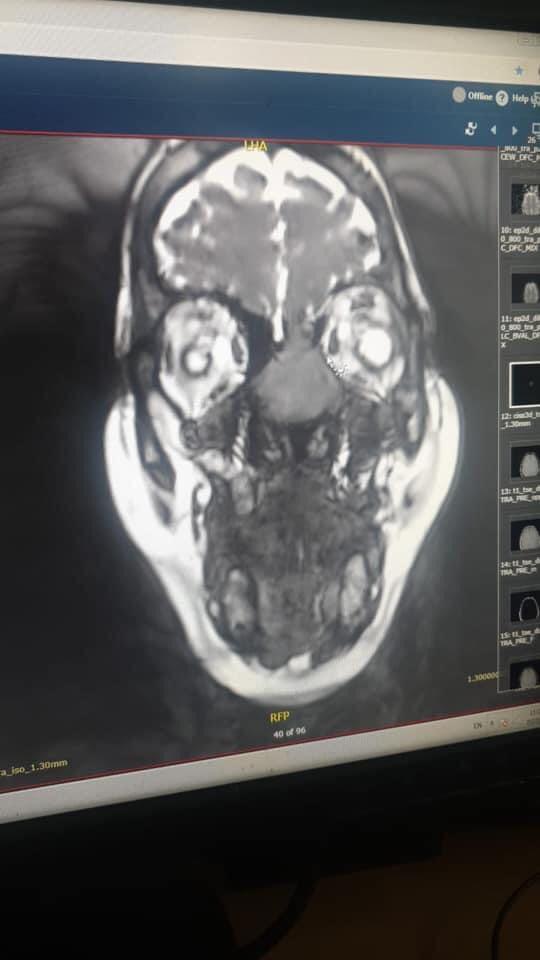

وأضاف الصفدي أن مثل هذه العمليات هي نتائج جهد مشترك من دائرة الأنف والأذن والحنجرة وأطباء الأشعة وفريق تخدير متخصص وكوادر تمريضية متخصصة ومؤهله.   وبين العقيد الطبيب نبيل الشواقفه انه في السابق أجريت للمريضة عملية لاستئصال الورم عن طريق فتح الأنف من الخارج وتم تشخيص الحالهrhabdomyosarcoma وبعد ذلك أخذت المريضة عدة جرعات من العلاج الكيماوي ولكن بعد فترة عادت المريضة تشكو من نفس الأعراض وبعد إجراء الفحوصات والأشعة اللازمة تبين وجود ورم دموي خبيث يملىء تجويف الجهة اليسرى من الأنف واختراقه للحاجز الأنفي مما أدى الى تآكل في عظم قاع الجمجمة وامتداد الورم بإتجاه الدماغ واتصاله بأغشية الدماغ الخارجية.

واضاف العقيد الطبيب الشواقفه أنه وبعد تشخيص الحالة تم إجراء استئصال للورم باستخدام المناظير الأنفية وبدون جروح خارجية وذلك بعد استحالة عمل قسطرة علاجية نظرا لخطورة هذا الإجراء وإحتمالية فقدان البصر وبناء على ذلك تم استئصال الورم جراحيا باستخدام المناظير وعمل رقع لقاع الجمجمة وتمت العملية بدون مضاعفات وآثار جانبية والحمدلله المريضة الآن تتماثل للشفاء وهي بصحةجيدة.